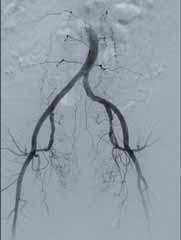

• Режим дослідження кінцівок (Dynamic Trace) передбачає рух деки столу за напрямком поширення контрастної речовини по периферичних судинах в режимі рентгенографії;